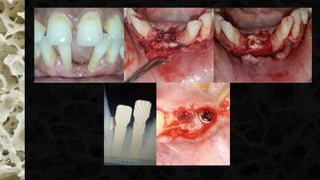

N. P. Lang,L. Pun, K. Y. Lau, K. Y. Li, and M. C. Wong, “A systematic review on survival and success rates of implants place d immediately into fresh extraction sockets after at least 1 year,” Clinical Oral Implants Research, vol. 23, supplement 5, pp. 39 –66, 2012.